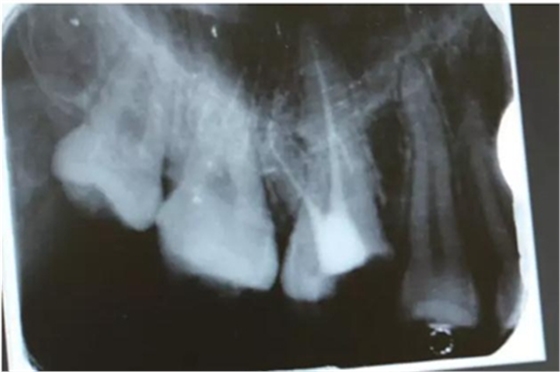

病例一 女性,20歲,大學(xué)生,要求補(bǔ)牙,檢查口內(nèi)可見A6大面積缺損,近中牙齦息肉,拍X片,根管充填物略差,但根周未見明顯陰影,口內(nèi)檢查無叩痛。建議患者冠延長手術(shù)+高嵌體修復(fù)。

患牙遠(yuǎn)中邊緣嵴完整,強(qiáng)度沒有降低,故擬保留遠(yuǎn)中邊緣嵴,高嵌體修復(fù)。首先去除腐質(zhì)及原墊底材料,流體樹脂+3M Z350XT樹脂墊底。局麻下行冠延長手術(shù)。在此需要提及個人的一個觀點(diǎn)。冠延長手術(shù)原則上要求3-6個月以上才能永久修復(fù)。但是個人喜歡后牙肩臺建立在齦上,所以修復(fù)后的修復(fù)體邊緣位于牙齦上方1mm,對牙周的愈合影響較小(如果為齦下邊緣則要慎重),故該患者術(shù)中按照齦上邊緣的設(shè)計(jì)進(jìn)行冠延長手術(shù)。以下為術(shù)中: